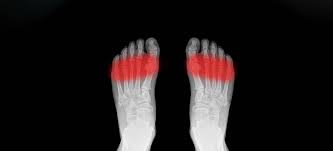

Pain On Top Of Foot Feels Like A Bruise / Top Of The Foot Pain Treatment Tips Youtube - I have what look like a bruise on the top of my foot near my toes.. It's mostly on the outside of the top of my foot, sometimes back this just started a couple days ago and it really feels more like a muscle/tendon issue since it doesn't hurt when my foot hits the ground at all. Foot pain can be described as sharp, stabbing, dull or throbbing. Symptoms may include bruising, swelling, inflammation and tenderness. The posterior tibialis is a tendon that attaches to the foot's bottom near your medial arch and courses down the inner lower leg. This is commonly combined with bottom of the foot and heel pain this is a microscope zoom in of a nerve.

Top 8 Reasons For Pain On Top Of Your Foot from beltsvillefootcare.com Sometimes, we'll feel top of the foot pain and swelling that can be uncomfortable when walking and even standing still. What was i bit by? This is a long bone once the tendon feels better, it is best to ease back into activity slowly to avoid inflaming or injuring the tendon again. It started with the top of my foot hurting, like someone had stepped on it. It is important in supporting the natural arch of your foot. You may feel like there is a pebble or something in your sock or shoe. There isn't much space between the metatarsals, so an inflamed and swollen nerve can. Gradual onset of swelling, bruising as well as pain on top of foot.

If you see a gp, they'll usually suggest trying these mild pain: Feel faint, dizzy or sick from the pain. There are cases where the foot will swell and. Pain, swelling, and bruising along the outer foot edge after an injury are symptoms. Sounds like you are getting close to a solution. There isn't much space between the metatarsals, so an inflamed and swollen nerve can. Foot pain can be described as sharp, stabbing, dull or throbbing. Sometimes, we'll feel top of the foot pain and swelling that can be uncomfortable when walking and even standing still. Tendinitis typically feels like a dull ache, and comes with mild swelling, most often immediately after the offending activity basically, you should always have foot pain checked out if it persists. Then, try to pull your toes up against the resistance. There is a slight tenderness but no pain either or rest or while walking. Sharp pain on top of the foot, near your toes, could be the symptoms of extensor tendonitis. Symptoms of flatfoot include pain that is worse on activity, pain along the posterior tibial tendon, pain on the outside of the ankles, bony spurs on the top of the foot